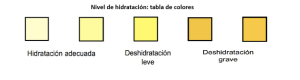

La mayor incidencia de cálculos ureterales se produce durante el verano Generalmente un mes después de la elevación de las temperaturas y presumiblemente debido a la deshidratación que conlleva a la concentración de orina. La orina concentrada tiene un pH inferior fomentando la cistina y la formación de cálculos de ácido úrico.

Consumo de agua

La ingesta baja de líquido (<1.200 ml / día) predispone a la formación de litiasis. La ingesta de agua “dura” (alto contenido de calcio) puede reducir el riesgo de formación de cálculos, por la disminución de oxalato urinario.

| Color de la orina y nivel de deshidratación. |